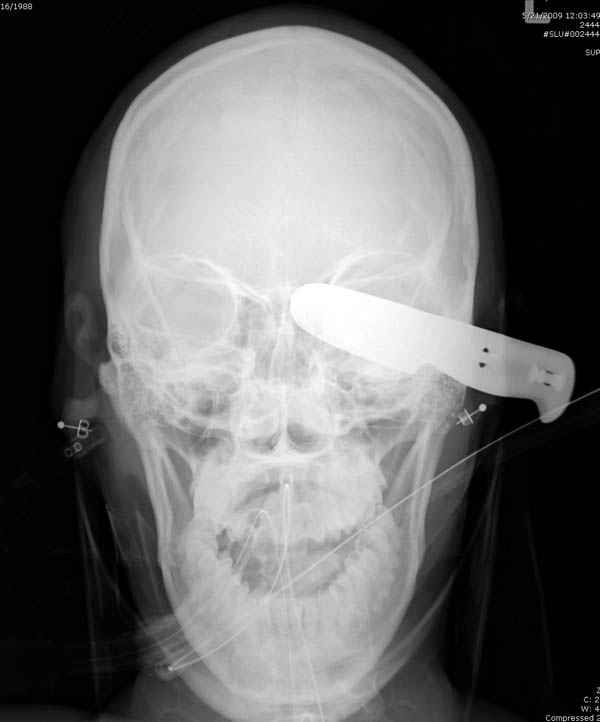

В своих выступлениях я рассказывал, что наши центры в мирное время по пенетрирующим травмам не уступает Ираку или Афганстану, и вот недавно к нам поступила больная 22 лет, травма "ножом в глаз" от бывшей подруги нынешнего "бой френда".

При поступлении в сознании, жаловалась на неприятные ощущения в глазнице.

По протоколу сделаны все необходимые исследования: рентген, ангиограмма с 3Д реконструкцией, где обнаружили что все жизненно важные сосуды не задеты, даже некоторые "сидят" изгибаясь на ноже.